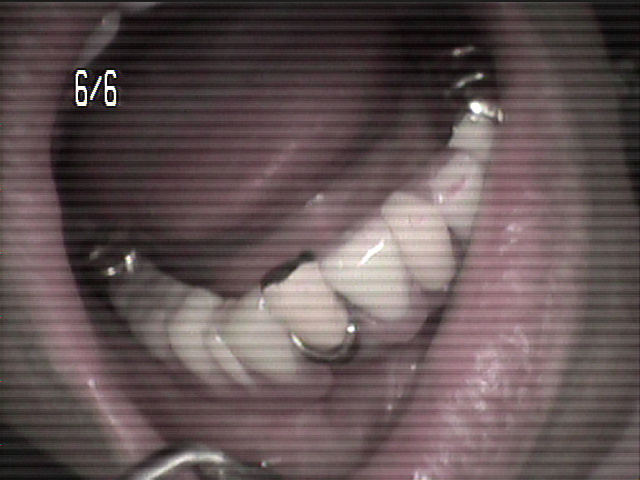

本日、出来上がりました自費の部分入れ歯ー下顎メタルプレートの症例です。

81歳の女性OUさんはとけも若々しいかたで、上下ともに、ぶぶん入れ歯ですが、今回は下顎の左右の奥歯のメタルプレートの入れ歯を新しく作りました。

自費によるメタルプレート義歯で、薄く丈夫な義歯として、とても舌感の良好な状態にすることができ、さらに自由な義歯の設計ができるため、残っているはにかける針金は白金加金で作成し、残存歯にやさしい設計となっており、舌に触れるバー部分はコバルトクロム合金で、丈夫に薄く作ってあります。

(参考代金;30万円)